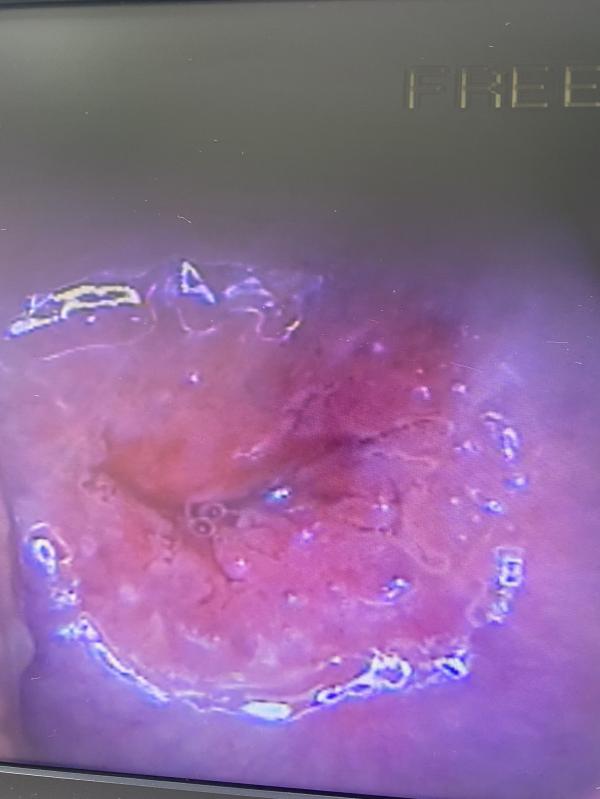

Это шейка нормальная которая должна быть да ?